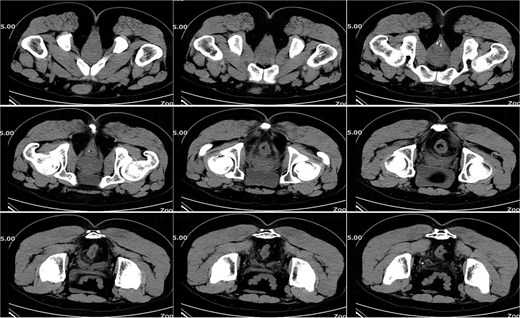

On postoperative Day 15, a complete blood count showed a white blood cell count of 9.12 × 109/l and a neutrophil percentage of 77.5%. Pelvic CT demonstrated rectal wall edema, anterior wall perforation, and partial absorption of the surrounding infection, indicating reduced infection severity compared to the previous scan on postoperative Day 10 (Fig. 3). Given the patient’s satisfactory response to antibiotic therapy and absence of ongoing infection signs, intravenous antibiotic treatment was discontinued.